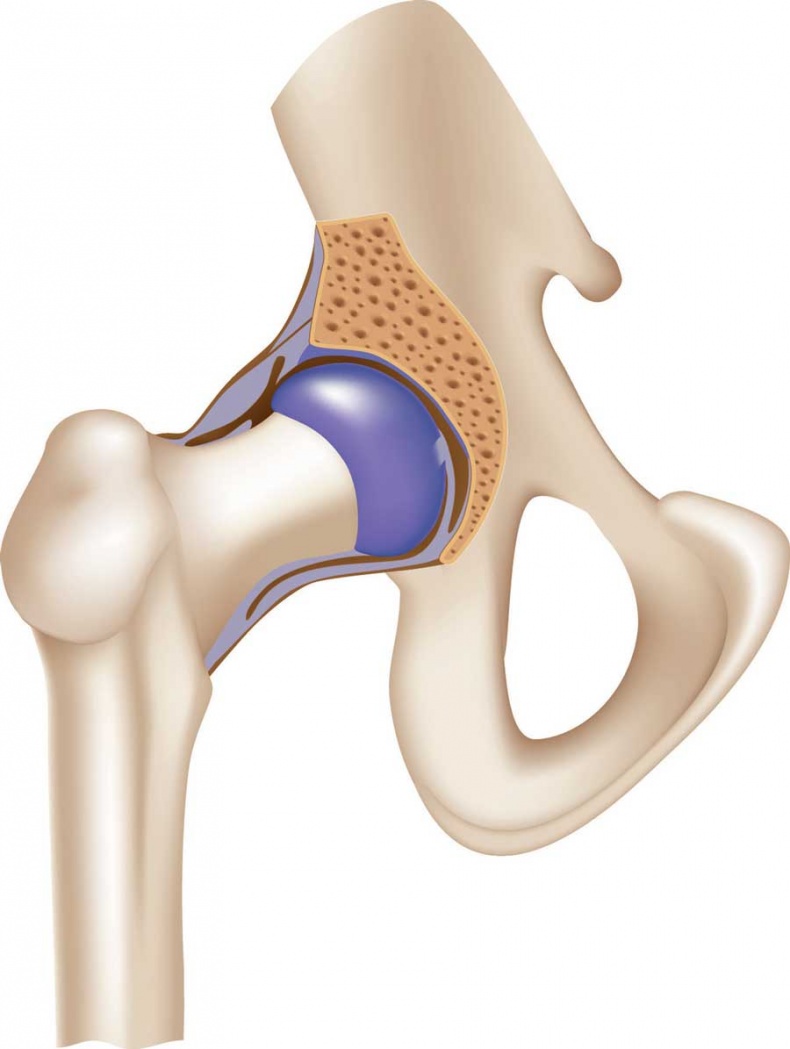

![]() Отделы позвоночника Движение позвоночника – результат работы многочисленных комбинированных суставов между позвонками. Он движется за счет действия скелетных мышц. Позвоночник способен наклоняться вперед, прогибаться (сгибание и разгибание), наклоняться вбок (отведение и приведение), а также скручиваться. Наиболее подвижны шейный и поясничный отделы. Химический состав костей взрослого человека следующий: 50 % воды, 15 % жира, 12 % органических веществ (белок, представляющий собой разновидность коллагена), 22 % неорганических веществ, а именно солей кальция в форме гидроксиапатита, и около 30 % органических веществ. Основные органические вещества кости – белки коллаген и оссеин. Сочетание волокон органического коллагена с солями кальция обеспечивает основные функции костей – прочность и упругость. Прочность – это способность противостоять внешним механическим воздействиям, упругость – возвращать первоначальную форму после окончания действия внешней силы. Минеральные вещества придают костям твердость и хрупкость, органические – гибкость и упругость. Благодаря сочетанию органических и неорганических веществ кости имеют большую прочность, что позволяет им выносить немалые нагрузки. ![]() Структура кости Соотношение органических и неорганических веществ с возрастом изменяется. В костях детей немного больше органических веществ, поэтому их кости более упругие, гибкие и реже ломаются. С возрастом в костях увеличивается доля неорганических веществ, из-за чего у пожилых людей кости менее эластичные и более хрупкие и могут ломаться даже при небольших травмах. Соединения костей связывают кости скелета в одно целое, обеспечивая им ту или иную степень подвижности. Различают три вида соединений: • непрерывные соединения, в которых полость между соединяющимися костями отсутствует, существует лишь прослойка соединительной ткани или хряща – неподвижные соединения; • переходная форма от непрерывных соединений к прерывным – симфизы, или полусуставы; имеют небольшую щель в хрящевой или соединительнотканной прослойке между сочленяющимися костями – эти образования обладают большой прочностью и очень ограниченной подвижностью; • прерывные (синовиальные) соединения или суставы; характеризуются наличием между костями полости и синовиальной оболочки, выстилающей изнутри суставную капсулу, – это подвижные соединения, а степень подвижности зависит от особенностей строения конкретного сустава. Сустав – самая распространенная и сложная форма соединения костей. Обязательными элементами любого сустава, независимо от места расположения и степени подвижности, являются суставные поверхности, суставная сумка и суставная полость. ![]() Соединение костей в коленном суставе (вверху – рентген, внизу – модель) ![]() Суставные поверхности костей, образующие сустав, плотно прилегают друг к другу. Они покрыты особым гиалиновым хрящом, чья гладкая поверхность и эластичность облегчают движение в суставе, смягчают испытываемые им толчки и сотрясения. Суставные поверхности костей окружает суставная капсула – оболочка из соединительной ткани. Обычно она крепится к костям в месте перехода суставной поверхности в надкостницу и прочно с ней срастается. Снаружи капсула укреплена связками, которые располагаются в местах наибольшей нагрузки. Суставные поверхности и капсула ограничивают собой небольшое герметично закрытое пространство – полость сустава, заполненную малым количеством вязкой синовиальной жидкости, роль которой заключается в уменьшении трения в суставах при движении. Благодаря отрицательному давлению в суставной полости поверхности костей тесно прилегают друг к другу. ![]() Суставная капсула ![]() Шаровидный сустав По форме суставных поверхностей различают плоские, цилиндрические, эллиптические и шаровидные суставы. Наименее подвижны плоские суставы, наиболее – шаровидные. Так как мы существуем в трехмерном пространстве, то в биомеханике суставов соответственно выделяют три оси вращения: фронтальную (правая – левая стороны, или наружная – внутренняя поверхности), сагиттальную (задняя – передняя поверхности) и продольную (вдоль сочленяющихся костей). В зависимости от формы суставных поверхностей в суставах может быть движение вокруг любой одной, двух или трех указанных осей (одно-, двух- и многоосные суставы). Вокруг указанных осей выполняются соответствующие виды движений. Вокруг фронтальной оси происходят сгибание и разгибание. При сгибании угол между сочленяющимися костями уменьшается (например, в локтевом суставе – угол между плечом и предплечьем). Во время разгибания движение идет в обратном направлении и происходит выпрямление (конечности или туловища). Вокруг сагиттальной оси осуществляются приведение и отведение. В случае отведения одна из сочленяющихся костей удаляется от срединной плоскости, при приведении – приближается к ней (например, отведение руки в сторону от туловища и снова приближение к нему). ![]() Наши двигательные возможности определяются прежде всего строением суставов Вокруг продольной оси кость вращается в разные стороны. Круговое движение – это последовательное перемещение вокруг всех осей, при котором свободный конец движущейся кости или конечности (например, кисти руки) описывает окружность. Размах (объем) движений в суставах зависит от многих факторов: • от разности угловых величин (выражаются в угловых градусах) сочленяющихся поверхностей (чем больше эта разность, тем больше размах движений); |